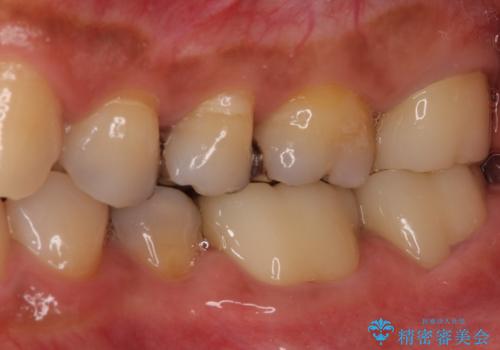

上の奥歯は一部神経を取り除くこととなりましたが、残った神経は正常な状態を保つことができました。

下の奥歯も、虫歯を取り除いて仮歯を装着したことで歯肉の腫れが引き、出血することもなくなりました。